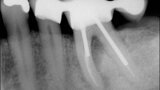

Buccal root of the bifurcated maxillary premolar—a danger zone during root canal therapy